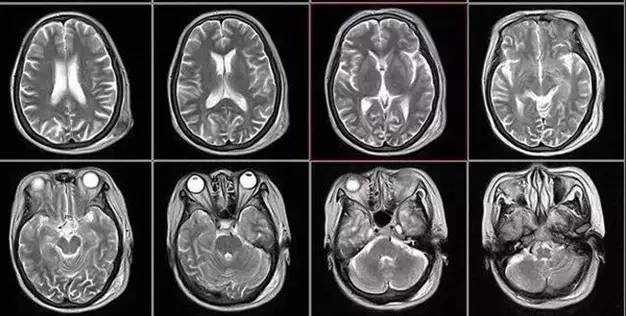

医学影像技术是什么在具体应用中?它可不止一种花样,而是个大家族,各显神通。X光就像快速扫描,适合看骨骼,价格也亲民;CT是三维成像,能层层剖析,连细小的肿瘤都逃不过它的“法眼”;MRI对软组织分辨率高,用于脑部、关节等,诊断精准;超声波则常用于孕妇检查,无创无痛,还能看到宝宝在肚子里动来动去,让人心里暖暖的。还有PET扫描,能显示代谢活动,用于癌症诊断,让隐匿的病灶无所遁形。你看,医学影像技术是什么?它是一个多面手,根据不同需求灵活运用,共同为健康护航。俺有时会听到有人说“影象技术”,其实标准说法是“影像技术”,但大伙儿都懂就行,这种小错误不影响理解,反而让聊天更接地气。